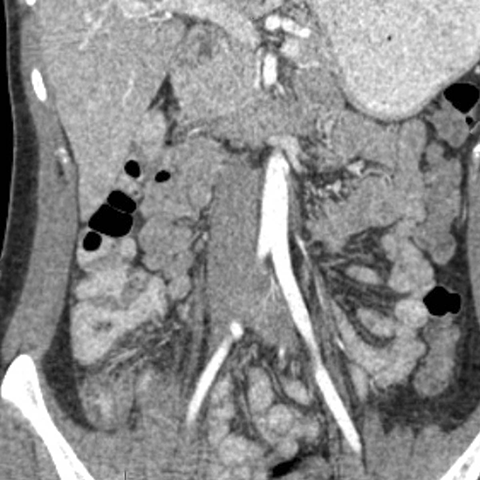

18 year-old male presents with a sudden onset of RLQ pain and rebound tenderness. [5 of 5]